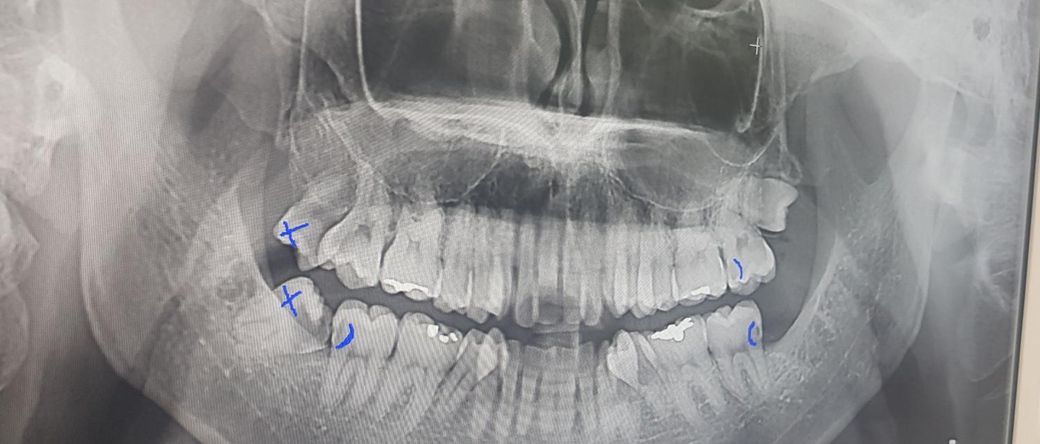

47번 어금니 쪽 치수복조술이 가능할까요?

사랑니는 이미 발치한 상태이고 47번 어금니에 대해

신경치료가 확실한 건 아닌데 가능성이 있다고 합니다

• 1번 째 사진

일단 충치가 신경 가까이 많이 근접한 것 같지는 않아 보이니 충치 제거하고 치수복제하는 약제 밑에 까는 것 시도해 볼 수는 있습니다. 일단 충치 제거해 보는 것이 우선입니다.